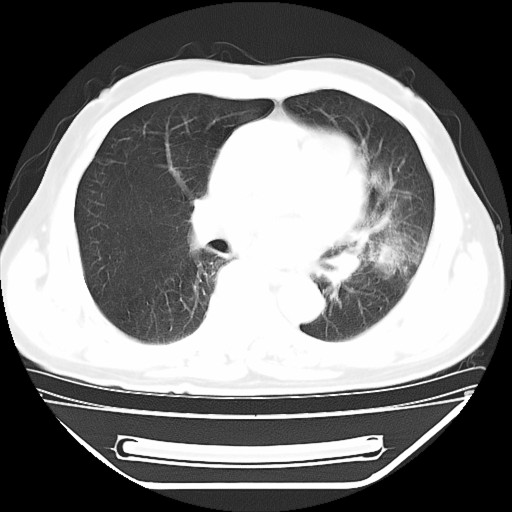

以下是引用hhcckk在2009-5-29 10:34:00的发言:[br]左下肺片絮状边缘模糊影,考虑感染,建议治疗后复查[br]